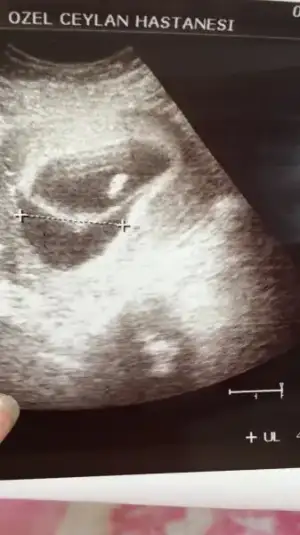

Kızlar bebısı de kanama alanınıda yukledm yayıl gıbı geldı banada oglum olcak kısmetse aman saglıklımolsunda bellımı olur netlesmeden buyumeden bısey almıcam zaten bana mıral verdız sız olmasanız delırırdım heralde allahın ıznıyle kuzucuklarımız dunyaya gelcek

Eklentiler

• 6A9DC044-AD7C-467A-B650-1C113C12753F.webp

6A9DC044-AD7C-467A-B650-1C113C12753F.webp

13 KB · Görüntüleme: 78